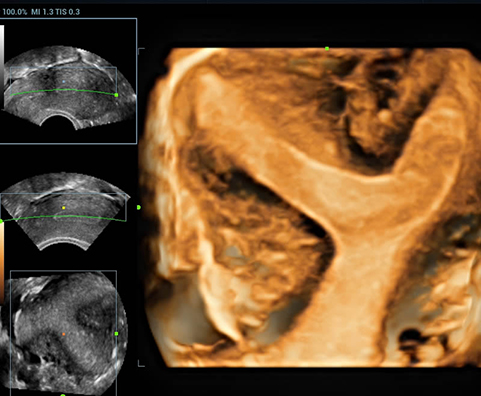

AdemÃĄs de una calidad superior de la imagen, el Resona 7 tambiÃĐn mejora las capacidades de investigaciÃģn clÃnica gracias al revolucionario V Flow para la evaluaciÃģn hemodinÃĄmica vascular y la adquisiciÃģn de planos mÃĄs inteligente a partir de un conjunto de datos 3D para el diagnÃģstico CNS fetal. Combinando el funcionamiento multitÃĄctil mÃĄs intuitivo basado en gestos y todas las funciones clÃnicas esenciales, el Resona 7 estÃĄ realmente encabezando nuevas ondas en la innovaciÃģn del campo del ultrasonido.